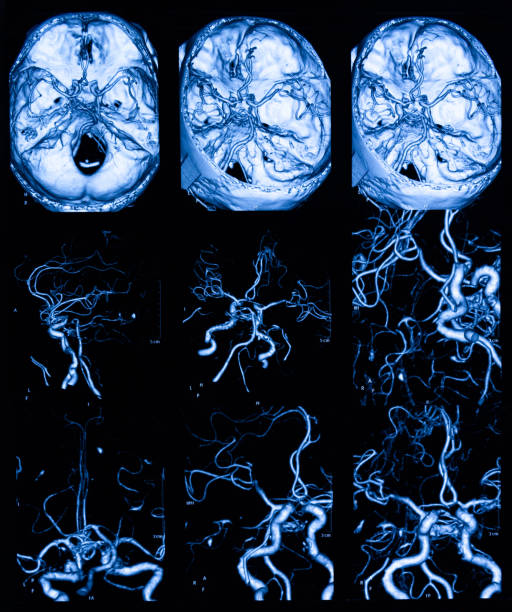

고혈압은 뇌출혈의 가장 큰 원인으로 볼 수 있는데 고혈압 환자라면 혈압이 갑작스럽게 상승하는데 이 때 산소와 영양소가 뇌로 들어가는 통로인 혈관에 변화를 일으키는데 혈관이 버티지 못하고 터지게 됩니다. 뇌동정맥의 기형에 의한 뇌출혈, 뇌동맥류 파열에 의하여 나타나며 잦은 흡연이나 다른 질병의 합병증으로 인해 발생할 수 있으며 뇌손상은 팔, 다리, 심하면 얼굴등 신체 일부분이 평생 마비시키며, 골든타임을 놓칠 경우 사망할 수도 있어 뇌출혈 전조증상에 대해 알고 있는 것이 좋습니다.

뇌출혈로 생명을 구했다하더라도 후유증을 무시하기는 어렵습니다. 일반적으로 수술을 하면 회복기간이 길지 않고 회복 가능성이 높지만 그러나 수술전 상태로 돌아가기 위해서는 수 개월이 걸릴 수 있습니다. 또한 회복에 도움이 되도록 이 작업을 지속적으로 수행해야 하며 뇌의 넓은 부위에 출혈이 발생하거나 상태가 심할 경우 완치가 어려울 수 있는데 이러한 회복과정에서도기억 상실과 만성 두통증상은 나타날 수 있습니다.

또한, 사지의 움직임에 비정상적인 운동신경을 일으켜 정상적인 기능을 할 수 없게 하는 편마비가 있으며, 심하면 사지마비가 옵니다. 언어의 중심에 문제가 있는 언어에 문제가 있어 말하기나 이해에 어려움을 일으키고 의사소통에 어려움을 겪을 수 있습니다. 그리고 후두엽에 뇌졸중이 생겼다면 시력 문제가 발생하기 때문에 시력에 문제가 이어질 수 있습니다.